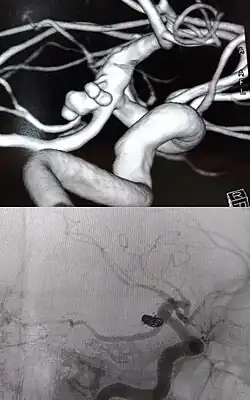

A embolização endovascular é geralmente realizada por um neurorradiologista intervencionista, com o paciente sob anestesia geral. Todo o procedimento é realizado sob orientação de imagem fluoroscópica (angiografia). Um cateter de guia é inserido através da artéria femoral e avançado para um local próximo ao aneurisma, após o qual a angiografia é realizada para localizar e avaliar o aneurisma. Depois disso, um microcateter é posicionado no aneurisma.

O tratamento utiliza molas destacáveis feitas de platina, que são inseridas no aneurisma usando o microcateter. Existe uma variedade de molas, incluindo as molas destacáveis de Guglielmi (GDC), que são malhas de platina revestidas com um biopolímero e hidrogel. Essas micro-molas também estão disponíveis em uma variedade de diâmetros, comprimentos e secções transversais.[12] Uma mola é inserida primeiramente ao longo da parede do aneurisma para criar um quadro, com o núcleo sendo preenchido com mais bobinas. Uma série de molas progressivamente menores também podem ser usadas. O sucesso é determinado pela injeção de contraste na artéria-mãe e qualitativamente determinando se o corante está fluindo no espaço do aneurisma durante a fluoroscopia. Se nenhum fluxo for observado, o procedimento é considerado finalizado.

As imagens médicas, particularmente a angiografia por tomografia computadorizada, podem ser usadas para gerar reconstruções 3D da anatomia específica do paciente. Quando combinado com CFD / FEA, a hemodinâmica pode ser estimada em simulações específicas do paciente, dando ao clínico ferramentas preditivas maiores para planejamento cirúrgico e avaliação de resultados para promover melhor a formação de trombo.[26][27] No entanto, a maioria dos modelos de computador usa muitos pressupostos de simplificação, incluindo paredes rígidas (não elásticas) para vasculatura, substituindo um meio poroso em lugar de representações de molas físicas e equações de Navier-Stokes para comportamento de fluido. No entanto, novos modelos preditivos estão sendo desenvolvidos à medida que o poder computacional aumenta, incluindo algoritmos para simulações de comportamento de molas in vivo.[12]